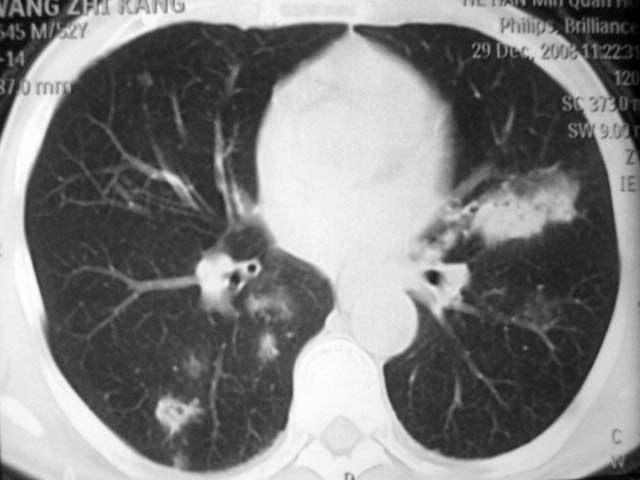

男,52岁,发热2月,糖尿病史。

抗结核治疗irpz方案,血糖未治疗,空腹15.9左右。症状无好转,左胸痛。

2、双肺见多发片状及结节状高密度影,大多数病灶中心均见“空泡征”。

3、纵隔内淋巴结肿大。

结果:两肺继发性肺结核并曲霉菌感染。